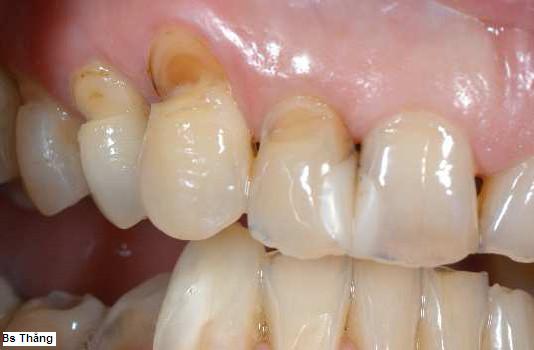

Chải răng không đúng phương pháp thường gây mòn cổ răng cửa và các răng hàm nhỏ 9 sô 4,5. Răng có thể bị mòn thành khía rãnh có hình chữ V ở mặt ngoài và gây nên ê buốt và có thể tiến triển gây viêm tủy răng do vi khuẩn xâm nhập qua lỗ thủng ở cổ răng này.

![]() | Mòn cổ răng do chải răng không đúng cách |

| | Mòn cổ răng hàm nhỏ hàm dưới |